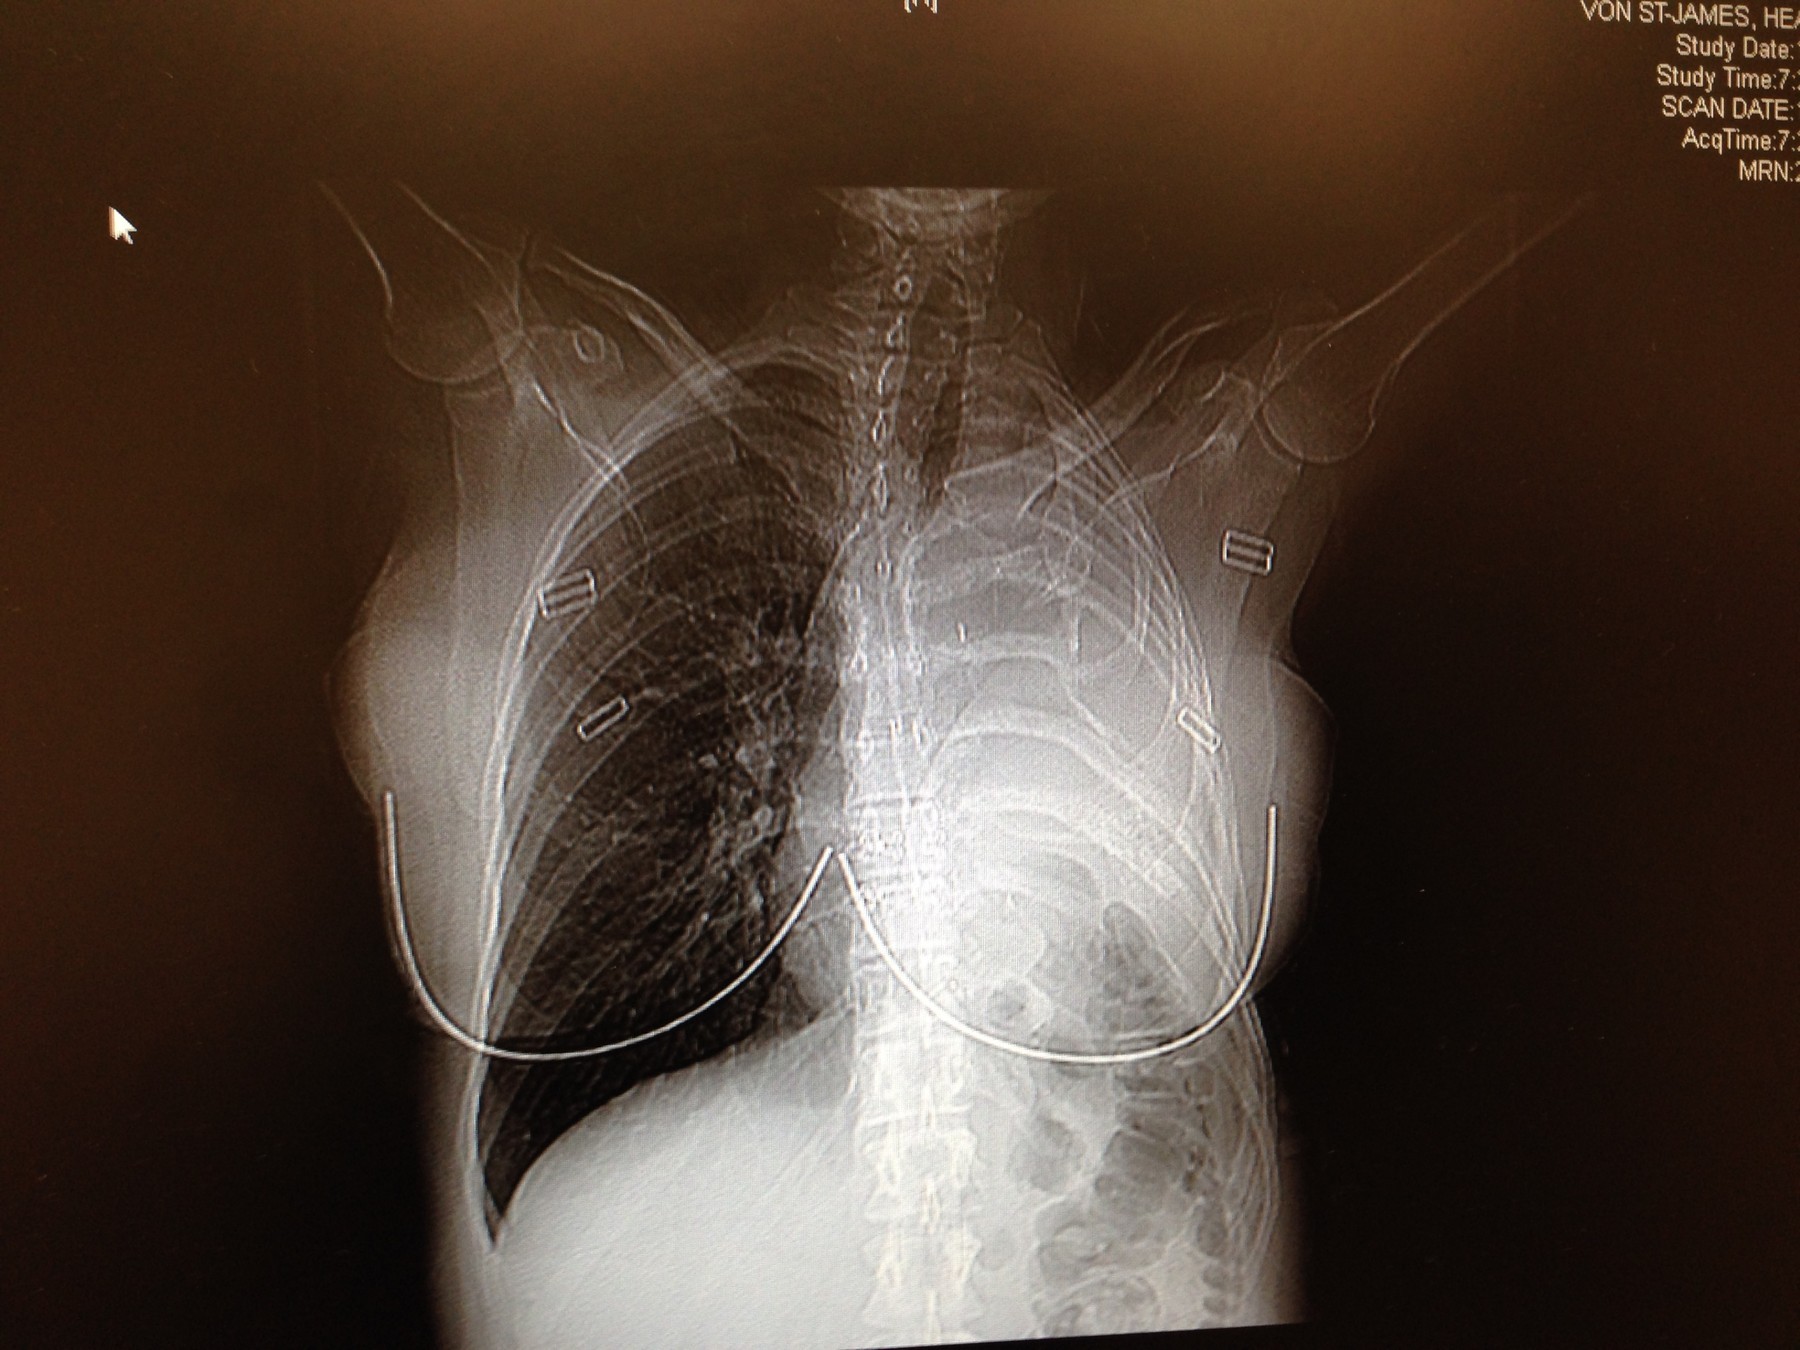

Následky tohto vystavenia sa prejavili až o desaťročia neskôr. Keď mala Heather 36 rokov a stala sa po prvýkrát matkou, začala pociťovať extrémnu únavu a horúčky. Príznaky najskôr pripisovala bežnému popôrodnému vyčerpaniu a návratu do práce kaderníčky. CT vyšetrenie však odhalilo šokujúcu pravdu: išlo o pleurálny mezotelióm, agresívnu formu rakoviny pľúc spôsobenú azbestom. Lekári jej dávali maximálne 15 mesiacov života.

Heather odmietla tento verdikt prijať. Odletela do Bostonu, kde podstúpila extrémne náročnú operáciu. Chirurgovia jej odstránili rebro, celé ľavé pľúca, pleuru, časť bránice a dokonca aj výstelku srdca, ktorú nahradili syntetickým chirurgickým materiálom Gore-Tex. Nasledovala priekopnícka „vyhrievaná“ chemoterapia aplikovaná priamo do hrudnej dutiny, ďalšie štyri kolá bežnej chemoterapie a 30 ožarovaní.

Zákrok bol úspešný a lekárom sa podarilo odstrániť všetky viditeľné stopy rakoviny. Dnes je Heather už takmer dve desaťročia zdravá. Život s jednými pľúcami jej síce prináša každodenné fyzické obmedzenia – zadýcha sa na schodoch a nemôže nosiť ťažké veci – no napriek tomu zasvätila svoj život pomoci iným.